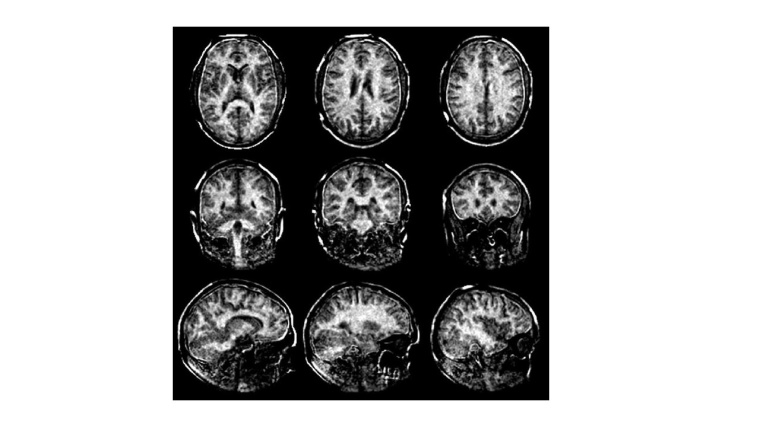

Multiple Sklerose mit neuem MRT-Verfahren sichtbar machen

ETH-Forschende haben ein neues Verfahren der Magnetresonanztomographie (MRT) entwickelt mit dem Multiple Sklerose (MS) frühzeitig erkannt und besser überwacht werden kann.

Das Verfahren bildet die Myelinscheiden im Gehirn genauer als bisher möglich ab. Der Verlust der Myelinscheiden ist ein wichtiges Merkmal der Multiplen Sklerose. Das neue MRT-Verfahren mit speziellem Kopfscanner könnte Forschenden auch dazu dienen, weitere feste Gewebetypen wie Bindegewebe, Sehnen und Bänder besser sichtbar machen.

Bislang ist es jedoch nicht gelungen, die Myelinscheiden so gut sichtbar zu machen, dass diese Information für die Diagnose und Verlaufskontrolle von MS dienen könnte. ETH-Forschende um Markus Weiger und Emily Baadsvik vom Institut für Biomedizinische Technik der ETH Zürich und Universität Zürich haben dies nun geschafft. Sie haben ein neues Verfahren der Magnetresonanztomographie (MRT) entwickelt, das den Zustand der Myelinscheiden genauer als bisher möglich abbildet. Die Forschenden testeten das Verfahren erstmals erfolgreich an gesunden Menschen.

Das neue MRT-Verfahren der ETH-Forschenden löst dieses Problem und misst den Myelingehalt direkt. Es versieht die MRT-Aufnahmen des Gehirns mit Zahlenwerten. Diese zeigen, wie viel Myelin an einer bestimmten Stelle im Vergleich zu anderen Bereichen des Bildes vorhanden ist. So bedeutet die Zahl 8, dass der Myelingehalt an dieser Stelle nur 8 Prozent von einem Maximalwert von 100 beträgt, was auf eine deutliche Ausdünnung der Myelinscheiden hinweist. Grundsätzlich gilt: Je dunkler der Bereich und je kleiner die Zahl im Bild, desto stärker sind die Myelinscheiden reduziert. Mit diesen Angaben könnten Ärzte den Schweregrad und Verlauf von MS besser einschätzen.